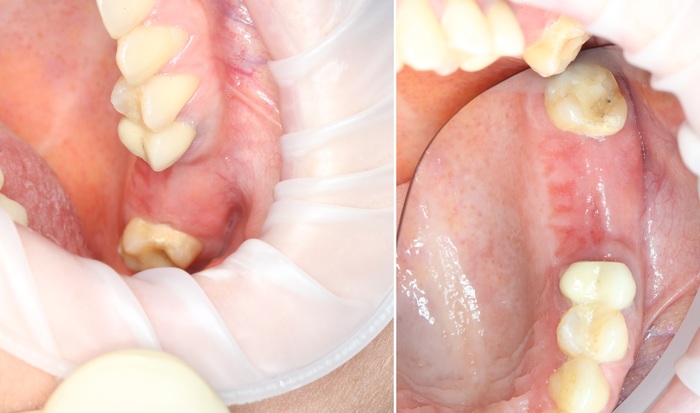

У пациента отсутствуют зубы 6 и 7 на верхней челюсти слева (некоторые фото сделаны при помощи зеркал, поэтому ракурс обзора может меняться):

Как и любая другая хирургическая манипуляция в полости рта, всё начинается с анестезии. Никто ведь не хочет испытать на себе все прелести стоматологической боли и мук.